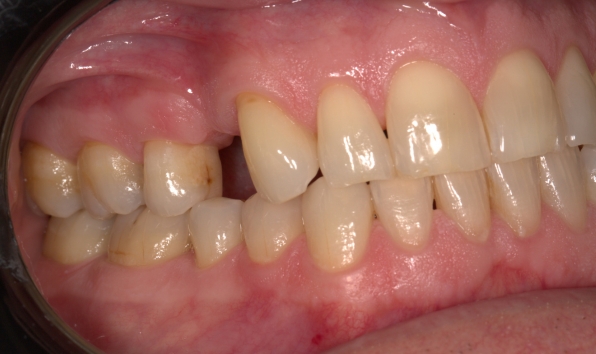

It’s not just about looks. When a tooth’s been lost, the ones next to the gap or opposite the gap start to drift, which can change your bite and make chewing or even talking a bit awkward. Filling that gap helps keep everything working right and makes life a whole lot easier.